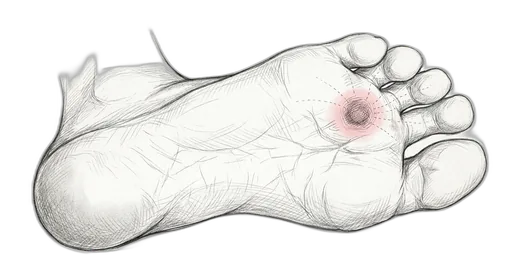

Foot & Ankle Exercise Guide

Choose your condition below to get started with exercises and stretches designed by Dr. Patish.

Pick your condition below, and you'll find your personalized exercise program — with medical illustrations, step-by-step instructions at three intensity levels, and clear guidance on when to call our office. Every protocol here is the same one Dr. Patish prescribes to patients in the clinic.

Forefoot & Toes